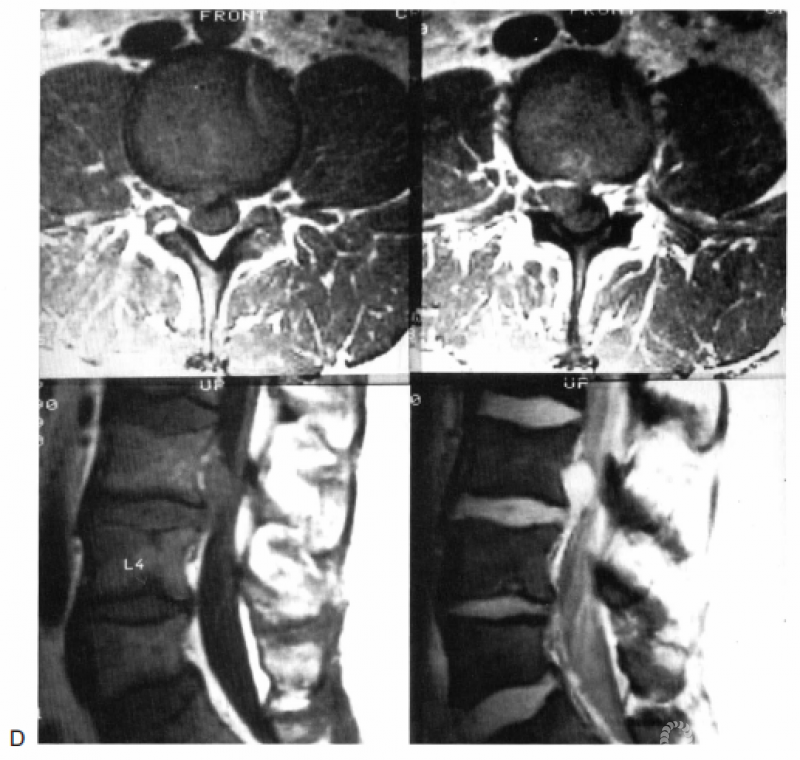

图18.10 A:图示为第2层的椎间盘突出,以椎间孔内的突出最为常见。箭头所示为椎间盘突出的移位路径;B:T1加权轴位MRI显示L3右侧椎间孔内的椎间盘突出(箭头);C:罕见的第2层椎间盘突出,位于椎管内。箭头所示为椎间盘突出的移位路径;D:T1加权轴位(上图)和矢状位(左下图)以及梯度回波矢状位(右下图)MRI显示第2层椎间盘突出